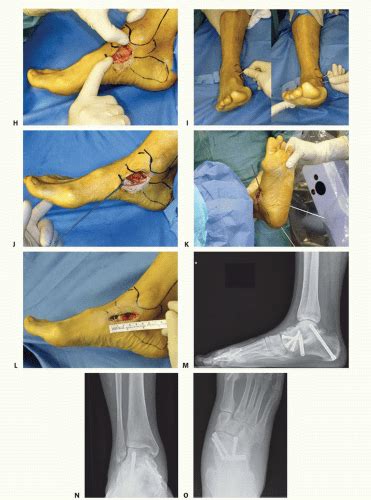

Medial Ankle/Deltoid Ligament Reconstruction | Musculoskeletal Key

Medial Ankle/Deltoid Ligament Reconstruction | Musculoskeletal Key musculoskeletalkey.com

ligament reconstruction medial ankle deltoid